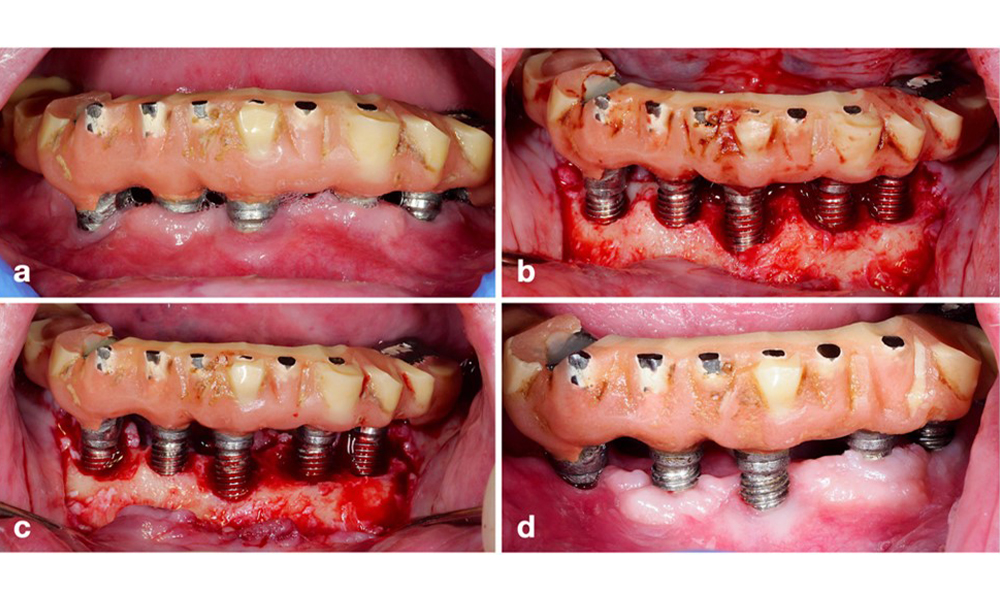

Die prothetische Restauration sollte bei einer nicht-chirurgischen ebenso wie bei einer chirurgischen Behandlung abgenommen werden, um einen besseren Zugang zur Implantatoberfläche zu ermöglichen. Die Wahl der chirurgischen Intervention (z. B. resektiv, rekonstruktiv oder eine Kombination) hängt von mehreren Faktoren ab: (1) Morphologie des Defekts (z. B. horizontal, Dehiszenz, intraossär oder eine Kombination) (Abb. 10), (2) Implantatoberfläche (also gedreht oder modifiziert/„rau“) und (3) Vorhandensein oder Fehlen einer ausreichend keratinierten und anhaftenden Schleimhaut.

Bei hauptsächlich horizontalen Knochenverlusten oder breiten Defekten mit begrenztem Knochenregenerationspotenzial sollte auf ein resektives Verfahren (also Gingivektomie und/oder apikal positionierter Lappen mit/ohne Knochenrekonturierung) zurückgegriffen werden (Abb. 11).

Für Implantate mit modifizierter Oberfläche und in Regionen, in denen eine Knochenregeneration unwahrscheinlich ist, sollte eine Implantoplastik in Erwägung gezogen werden. Dieses Verfahren beinhaltet die Entfernung des Implantatgewindes und die Glättung der mikrostrukturierten Implantatoberfläche mit rotierenden Instrumenten (Abb. 12). Dieses Verfahren erleichtert die umfassende Dekontamination der Implantatoberfläche und verbessert vor allem die postoperative Biofilmkontrolle (Bertl und Stavropoulus 2021; El Chaar et al. 2020; Geremias et al. 2017). Infolge mangelnder klinischer Evidenz wird die Rolle der Implantoplastik kontrovers diskutiert (Herrera et al. 2023; Ramanauskaite et al. 2021). Allerdings ließen sich die Bedenken im Hinblick auf Entzündungen durch die unvermeidliche Anlagerung von Titanpartikeln sowie auf ein erhöhtes Risiko von Implantatbrüchen infolge verminderter Implantatfestigkeit nicht bestätigen (Stavropoulos et al. 2019).